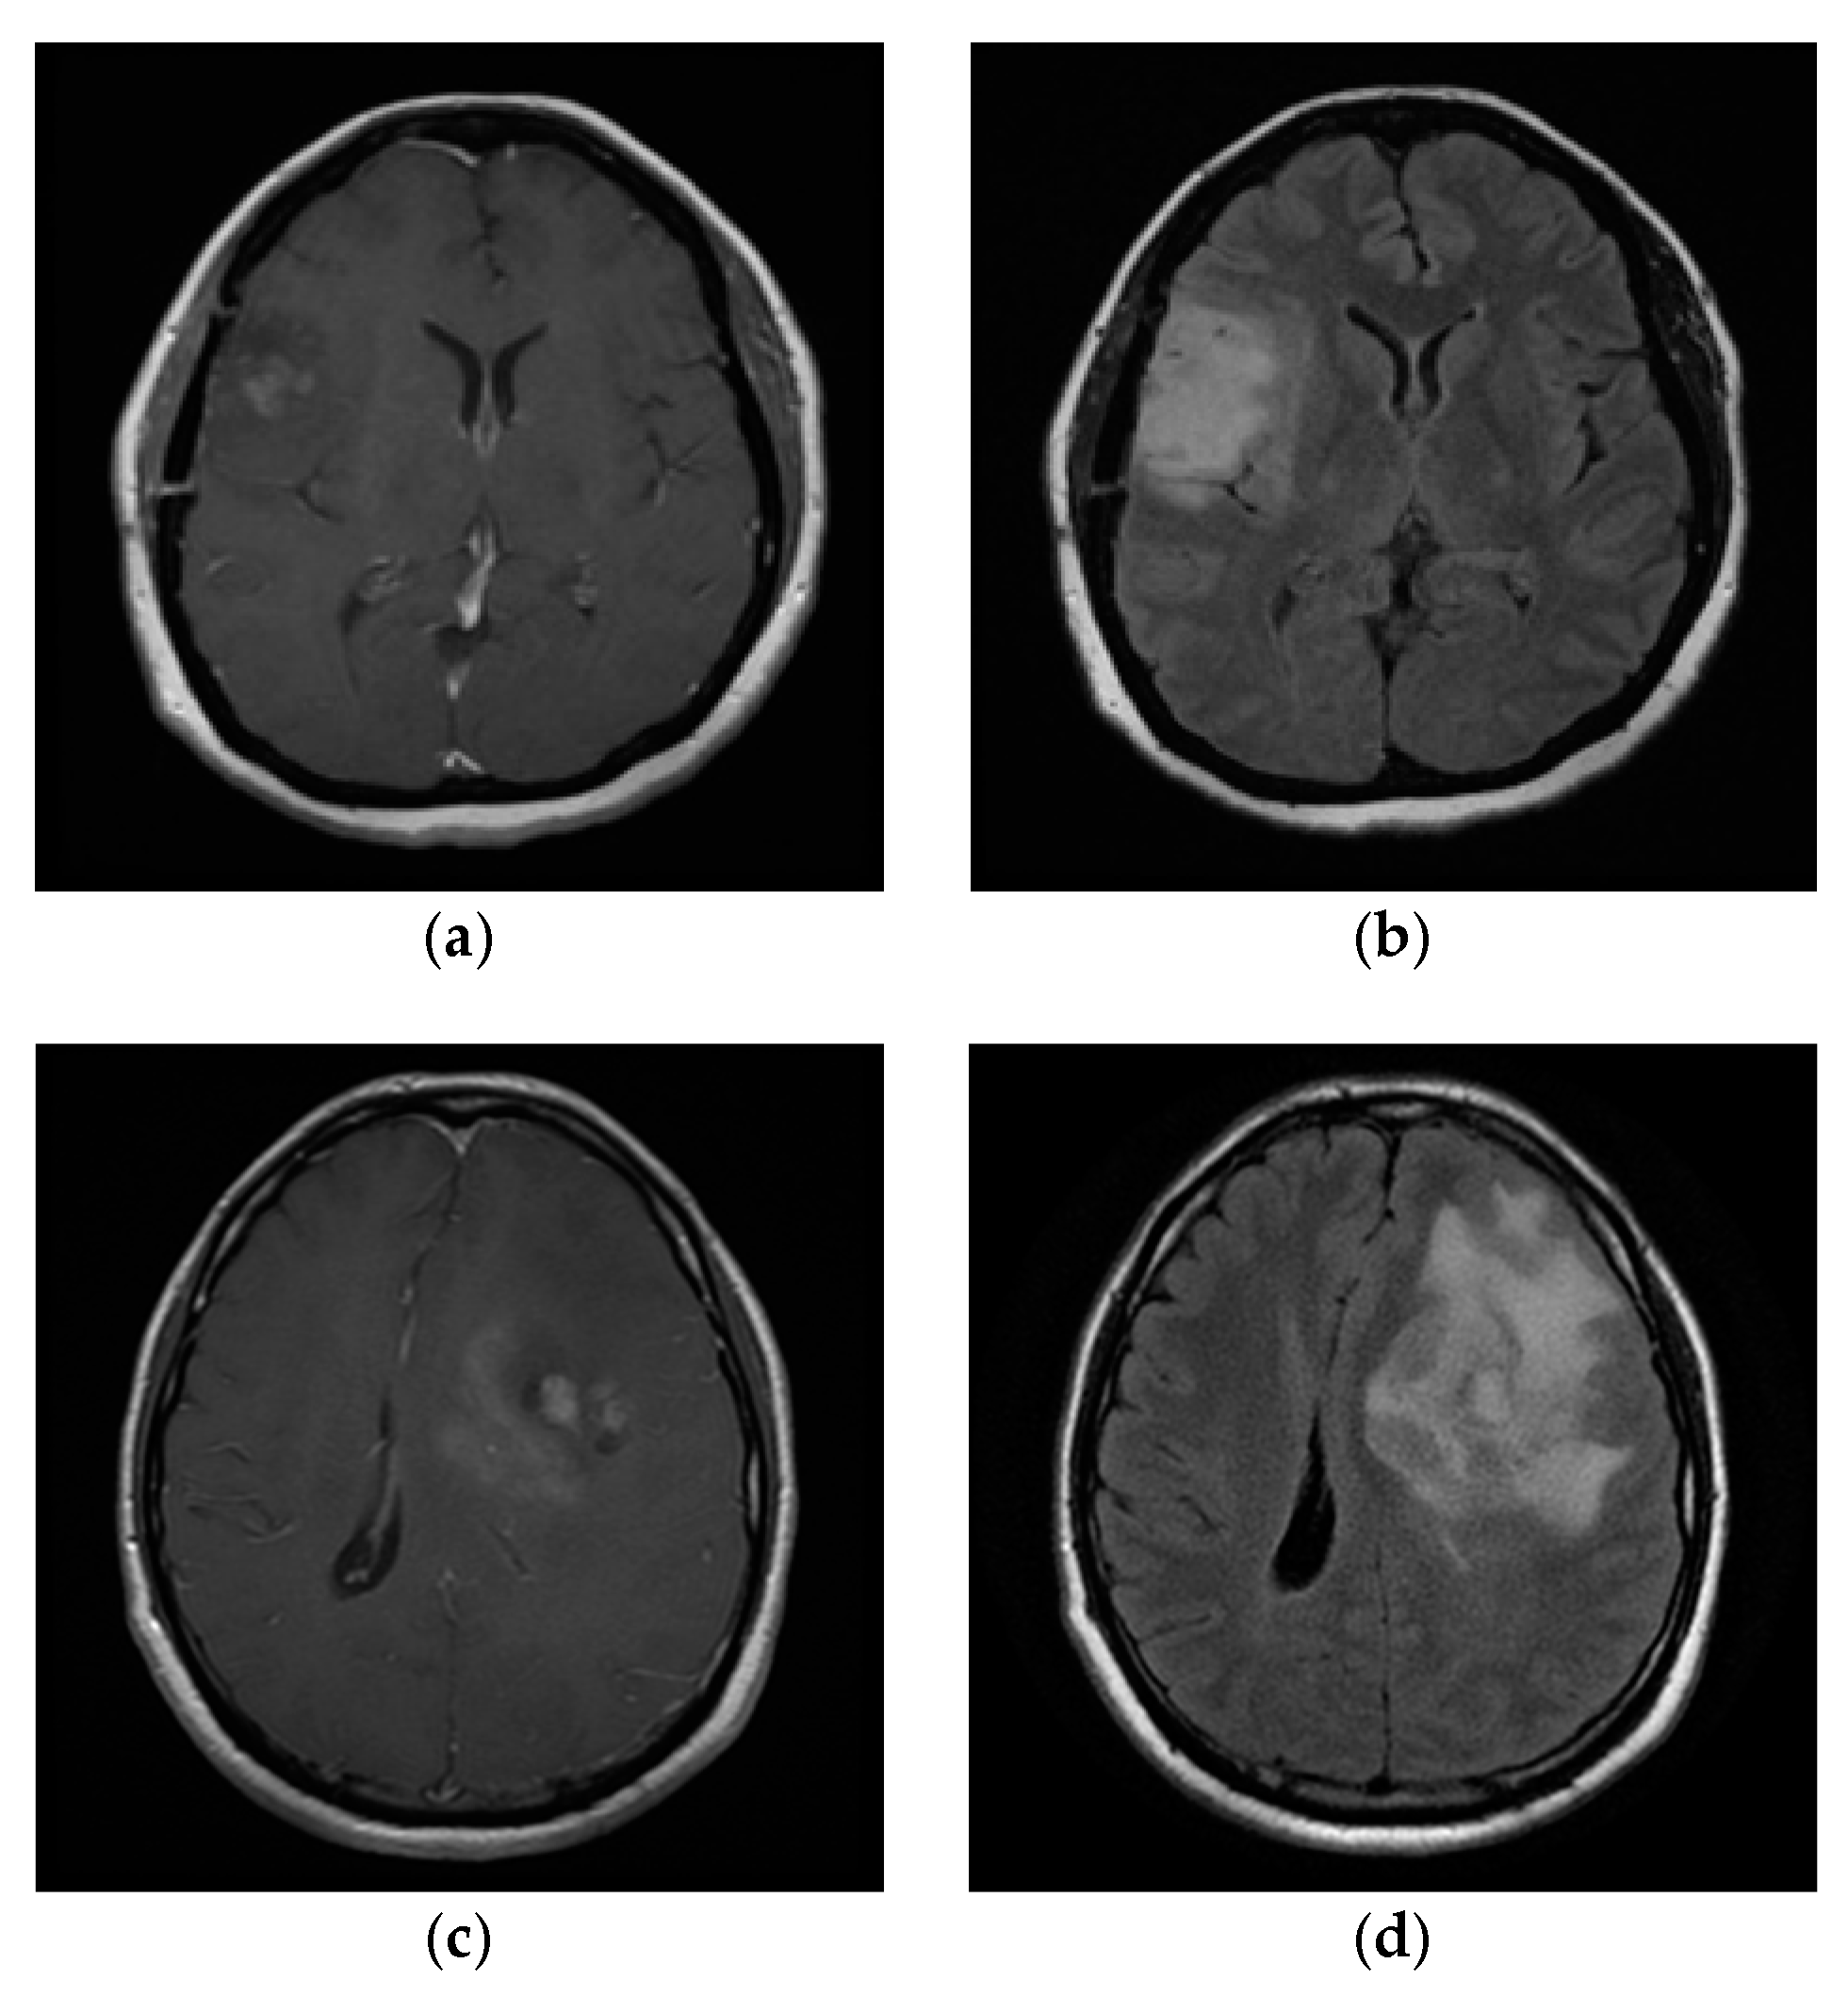

5.2. Application for MRI-Based Brain Tumor